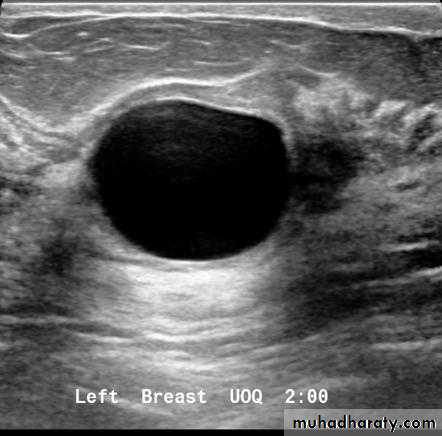

Cysts can be simple fluid-filled sacs (known as simple cysts) or can be partially solid (known as complex cystic and solid masses). Simple cysts are benign (not cancer) and don’t need to be biopsied. If a mass is not a simple cyst, it is of more concern and might need to be biopsied to be sure it isn’t cancer

CYST